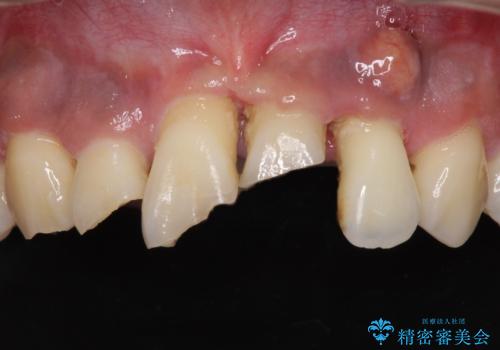

- ソーシャルメディアでのゲームに夢中になっている最中に車と接触し、前歯の抜歯を余儀なくされた患者様です。

初診時では前歯が保存できる可能性も模索しましたが、損傷が激しく3歯を抜去することとなりました。

保存となった隣在歯も神経が失活していており、補綴治療が必要であったので、オールセラミッククラウンにて補綴治療することとしました。